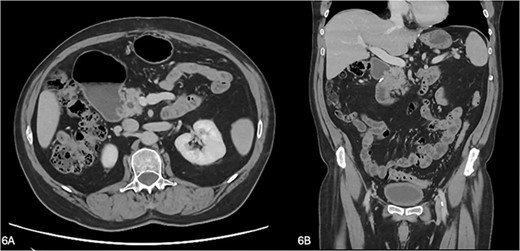

The patient represented on the eighth postoperative day with recurrent reflux and belching symptoms. A repeat CT and EUS were performed which demonstrated a 1–2-cm collection adjacent to the second part of duodenum where the annular pancreas had been divided. This was aspirated by EUS and revealed a lipase of 88 931 U/l, consistent with a small contained pancreatic leak. At the same procedure, he underwent duodenal dilatation with a CRE™ balloon dilator placed under fluoroscopic guidance to dilate the duodenal lumen to 20 mm diameter. This has since resolved his symptoms and he has remained well. A repeat CT at 4 months showed improvement of the long-standing gastric distension and first part of duodenum at the previous transition point and resolution of the periduodenal fat stranding and duodenal wall thickening (Fig. 6).

(A, B) A repeat CT at 4 months showing improvement of the gastric and duodenal distension proximal to the previous transition point and resolution of the periduodenal fat stranding and duodenal wall thickening.